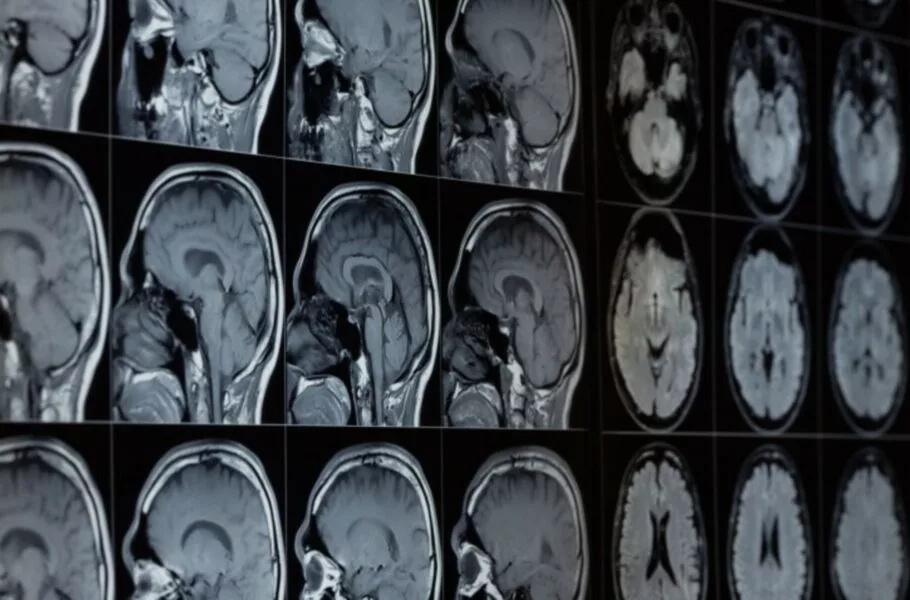

تشخیص سرطان و انواع بیماری‌ها با هوش مصنوعی آسان‌تر می‌شود.

مایکروسافت هوش مصنوعی جدیدی را توسعه داده است که می‌تواند برای آنالیز تصاویر پزشکی کاربرد داشته باشد و برای مثال تومورها را پیدا کند. این مدل هوش مصنوعی براساس GPT-4 از OpenAI ساخته شده است.

براساس اعلام رسمی مایکروسافت، ابزار هوش مصنوعی جدید این شرکت BiomedParse نام دارد. از این ابزار می‌توان برای ارزیابی سی‌تی‌اسکن، ام‌آرآی، تصاویر اشعه ایکس، اولتراسوند و انواع دیگر تصاویر پزشکی برای شناسایی مشکلات احتمالی یا تشخیص انواع سلول‌ها یا سایر پدیده‌های بیولوژیکی در یک تصویر استفاده کرد.

به گفته مایکروسافت، پزشکان برای استفاده از این ابزار لازم است ابتدا متنی را به آن بدهند؛ برای مثال، پزشکان می‌توانند عبارت «سلول‌های پاتولوژیک» را تایپ کنند و هوش مصنوعی محل قرارگرفتن آنها در تصویر را شناسایی می‌کند. مایکروسافت ادعا می‌کند ابزار BiomedParse تاکنون توانسته مواردی همچون تومورها، ملانوم، ادم سیستوئید ماکولا، عفونت قفسه سینه کووید ۱۹ و گلیوما مغز و سایر بیماری‌ها را شناسایی کند.